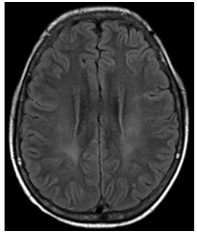

Figure 2 FLAIR images showing no abnormalities.

Figure 3 FLAIR images showing no abnormalities.

Figure 5 with no correspondence in FLAIR images.

Figure 7 (FLAIR) now it is possible to identify correspondently high signal FLAIR images.

Figure 8 (FLAIR) now it is possible to identify correspondently high signal FLAIR images.